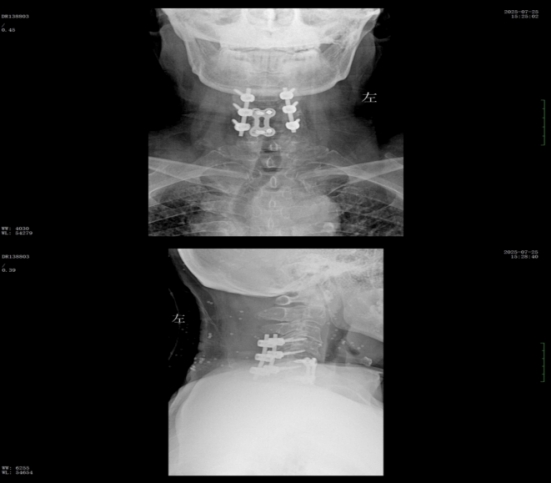

經(jīng)過精準(zhǔn)手術(shù)和術(shù)后系統(tǒng)的康復(fù)治療,患者神經(jīng)功能得到明顯恢復(fù),四肢肌力及感覺逐步改善,術(shù)后肌力達(dá)到IV級左右。復(fù)查X線顯示內(nèi)固定位置理想,患者非常滿意。出院之際,患者及家屬對衡陽市中心醫(yī)院的醫(yī)療技術(shù)、護(hù)理服務(wù)及醫(yī)聯(lián)體轉(zhuǎn)診效率均給予高度評價。

術(shù)后x線內(nèi)固定位置理想